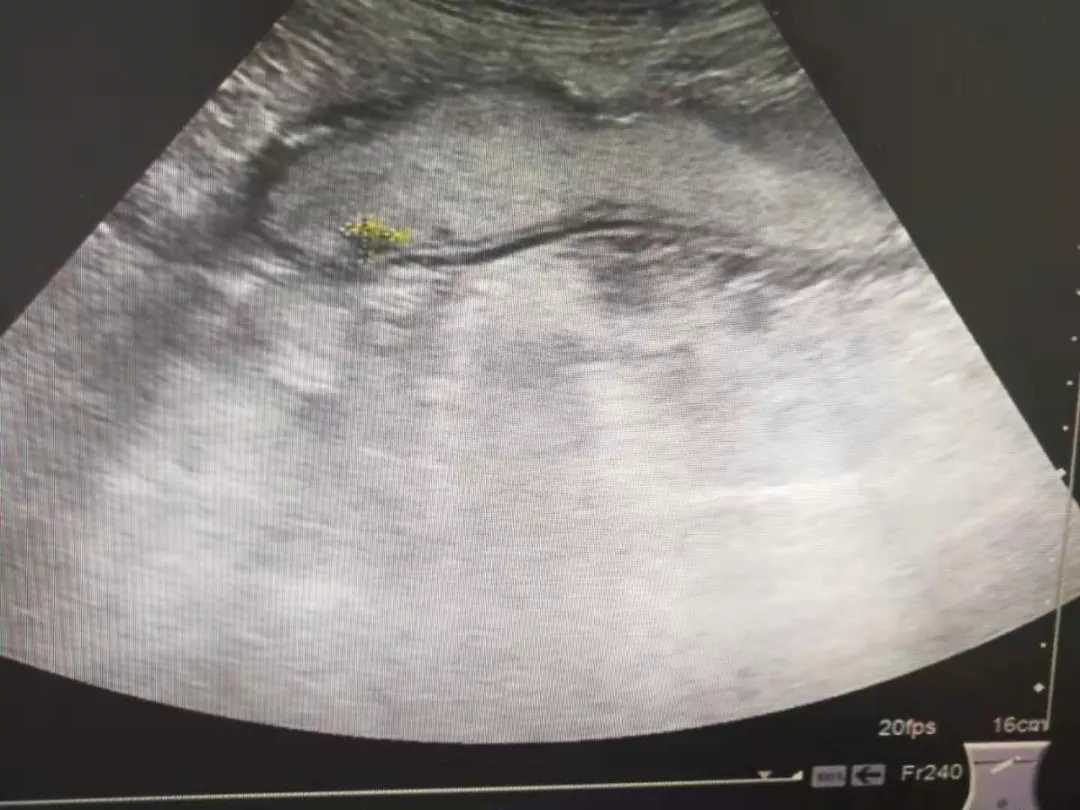

胃体息肉